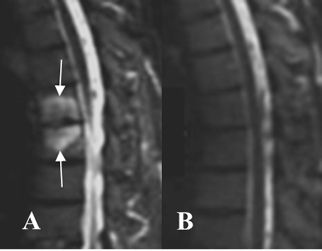

Fig 59 J. Espondilodisquitis.

A y B: RM STIR. Edema trabecular de las placas terminales y rodeando un espacio intervertebral, por espondilodisquitis. En un control 10 meses después de iniciar el tratamiento, han desaparecido los cambios inflamatorios.